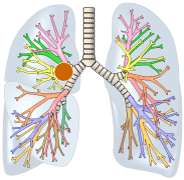

左図:肺野型肺がんは気管支の細い部分に発生した肺がんです。

肺野型肺がんは細い気管支や肺胞の部分の肺がんなので、痰の検査を行ってもがん細胞を発見することは難しいです。気管支鏡を行っても病変を直接観察することができないので、レントゲンの透視を使用しながら病変の位置を確認して、針金の先に付いたピンセットやブラシで細胞を取らなくてはなりません。CT検査を行って、病変の位置を確認し針を刺す検査を行うことがあります。肺門型と異なり太い肺動脈や肺静脈がないので比較的安全に針を刺す検査を行えるのです。